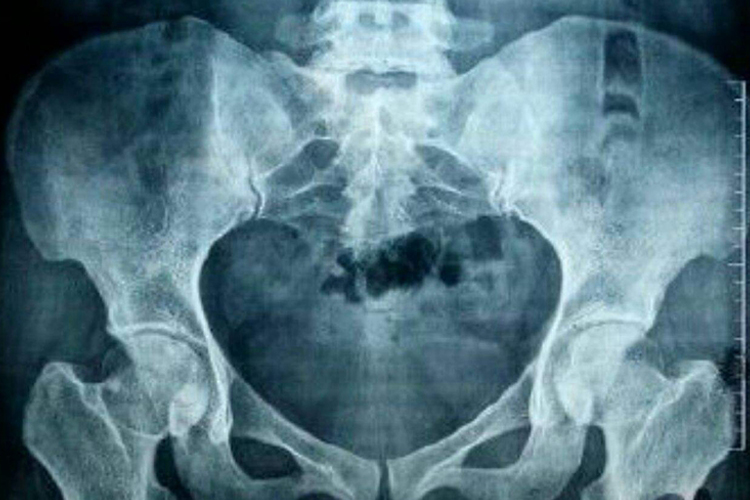

盆骨骨折采取保守治疗后的完全恢复时间因人而异,受到多种因素的影响,一般在6-24个月,与骨折情况、并发症、身体状况、康复训练和个体差异等方面有关,患者在治疗过程中应积极配合,以促进尽早康复。

恢复期间保持营养均衡的饮食,摄入足够的钙质、蛋白质和维生素等营养物质,以促进骨折愈合,定期到医院进行X光检查或CT扫描,了解骨折愈合情况和康复进展